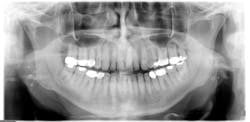

For the most part, the concretions go undetected unless they are observed in a panoramic radiograph (see Figure 1). Patients may report coughing up what is described as firm pieces of food or debris that have an odor to them. The patient may also complain of halitosis and a foul taste. In rare instances, the patient may report odynophagia (burning pain or squeezing pain when swallowing) and dyspnea (difficulty in breathing or shortness of breath). Patient may also complain of ear pain.

Radiographic assessment: Small, multiple, radiopaque, ill-defined, calcareous objects are seen on the radiograph (see Figure 1). The radiograph presented in this column was taken in 2015 of a 76-year-old male.

These opacities are not limited to the palatine tonsils but may also be seen in accessory lymphoid tissue. Sometimes what is referred to as "ghost images" appear on a pantomograph, making a pseudotonsillolith visible on the opposite side. This occurs because the object is located between the X-ray source and the center of rotation of the cassette. The patient may have oral calcifications bilaterally or unilaterally, so further evaluation is always needed.